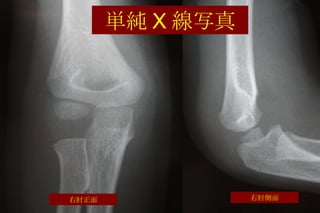

単純 X 線写真 右肘正面 右肘側面

単純 X 線写真 右肘正面 右肘側面 上腕骨顆上骨折

上腕骨顆上骨折の基本 小児期に起こる全骨折の約 17% を占める頻度の高い骨折 6 歳から 8 歳の男児に多い 約 97% の患者が肘を伸展位にして受傷 治療方法は保存療法から手術療法までいろいろ 不適切な治療でさまざまな合併症がおこる

X 線写真での診断のポイント Fat   pad   sign 上腕骨の後方への転位